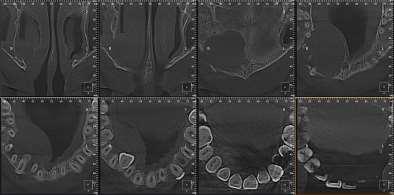

FIGURA 1 (TOMOGRAFIA VISTA FRONTAL)

RECONSTRUCCION 3D DE LA ZONA A ESTUDIAR

Las reconstrucciones tridimensionales nos permiten una visualización detallada y precisa de las estructuras vecinas a la pieza retenida, superando las limitaciones 2D de las radiografías convencionales, también ayudara en este caso para la planificación quirúrgica y posterior tratamiento de ortodoncia.

En este caso podemos observar una lesión de diámetro considerable de bordes corticalizados y forma irregular proyectada en el maxilar superior en el cuadrante 1, que se extiende desde distal de la pieza 1.1 hasta distal de la pieza 1.5, desde el tercio apical de las piezas 1.2 – 1.4 y 1.4 por vestibular y desde cervical por palatino. Se evidencia también a la pieza 1.3 retenida desplazada el ápice hacia la cortical palatina y la corona hacia la cortical palatina

CORTES AXIALES

Con la evaluación de la tomografía volumétrica en cortes axiales y transversales se observa la expansión y adelgazamiento de la tabla ósea vestibular y palatina legando a dicha pérdida ósea, también se observa el desplazamiento de la pieza 1 3 la cual se encuentra retenida y desplazada hacia la basal vestibular.

CONCLUSION

CORTES SAGITALES

A nivel de los cortes sagitales y coronal verificamos la extensión de la lesión y evidenciar el desplazamiento de las piezas 1.2 a mesial y 1.4 hacia distal a causa de la retención de la pieza 1.3 y expansión de la lesión